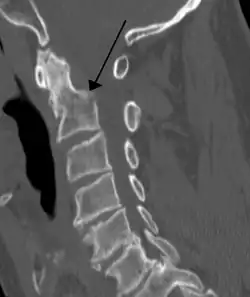

Sagittal reconstruction of a CT scan showing a cervical fracture with dislocation at the level of C6/7

On CT scan or X-ray, a cervical fracture may be directly visualized. In addition, indirect signs of injury by the vertebral column are incongruities of the vertebral lines,[7] and/or increased thickness of the prevertebral space:[8]